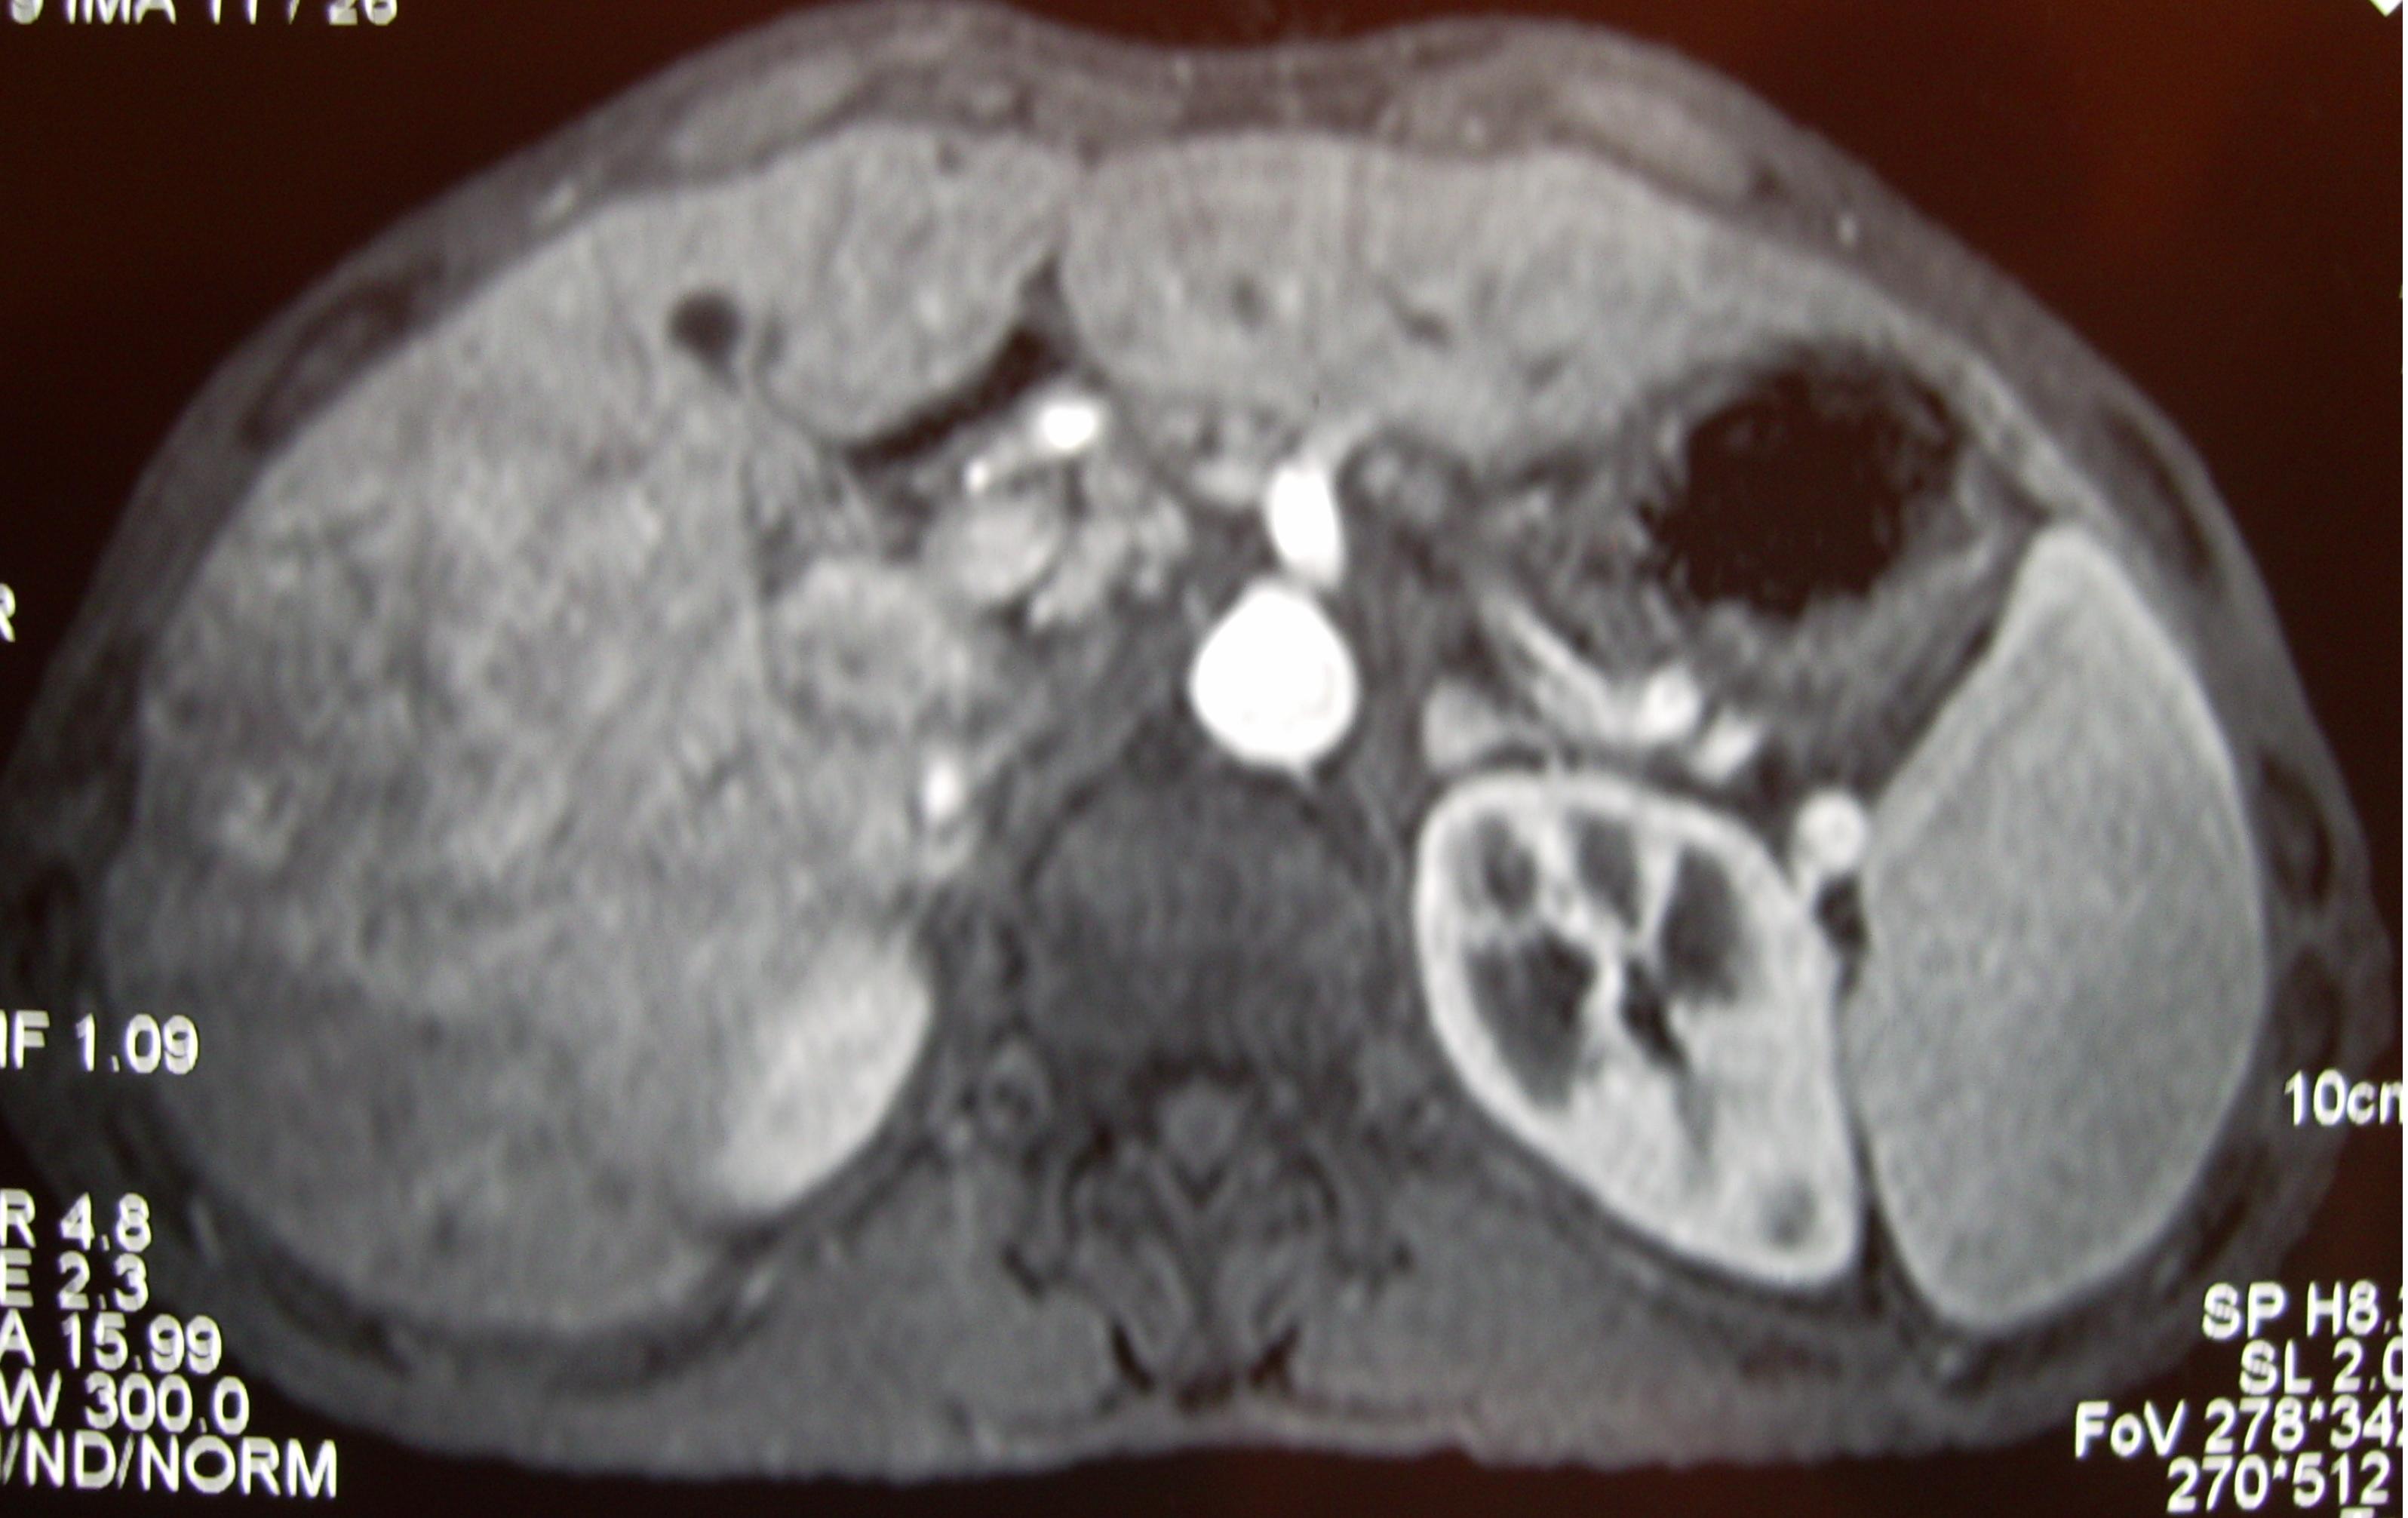

病因介绍:24岁女性,因大便性状改变、反复右上腹疼痛不适于2001年4月到医院就诊。上腹部增强磁共振发现左右肝弥漫性肿块,边界不清楚,在动脉晚期呈现不均匀强化,肝脏表面多发节结,不光滑,并且有脾肿大。血清甲种胎儿球蛋白超过1200ng/mL,血清铁蛋白626.50ng/mL,均明显升高。肝肿块穿刺活检结果为原发性肝细胞肝癌。诊断结果:原发性肝癌IIIb期,pT4N0M0,肝硬化,脾肿大,肝功能Child B级。

影像学检查发现左右肝弥漫性肿块